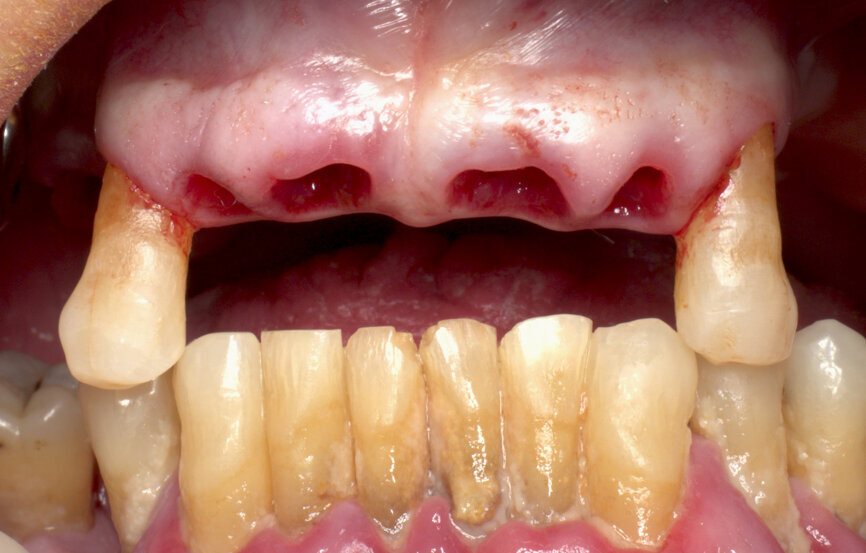

The surgery was performed under local anaesthesia and with patient monitoring by an anaesthesiologist using conscious intravenous sedation with midazolam and pulse oximetry monitoring. Removing failing teeth was the first task, keeping in place those teeth with less mobility and in strategic positions to maintain antagonist contacts, and trying to keep the same preoperative bite (Fig. 4).

Extraction sockets were fully debrided with a bur to remove all of the granulomatous tissue. Gingival trimming was also performed on those gingival parts with deep pockets. Cleaning with hydrogen peroxide and saline was the final step, obtaining fresh places for the implants.